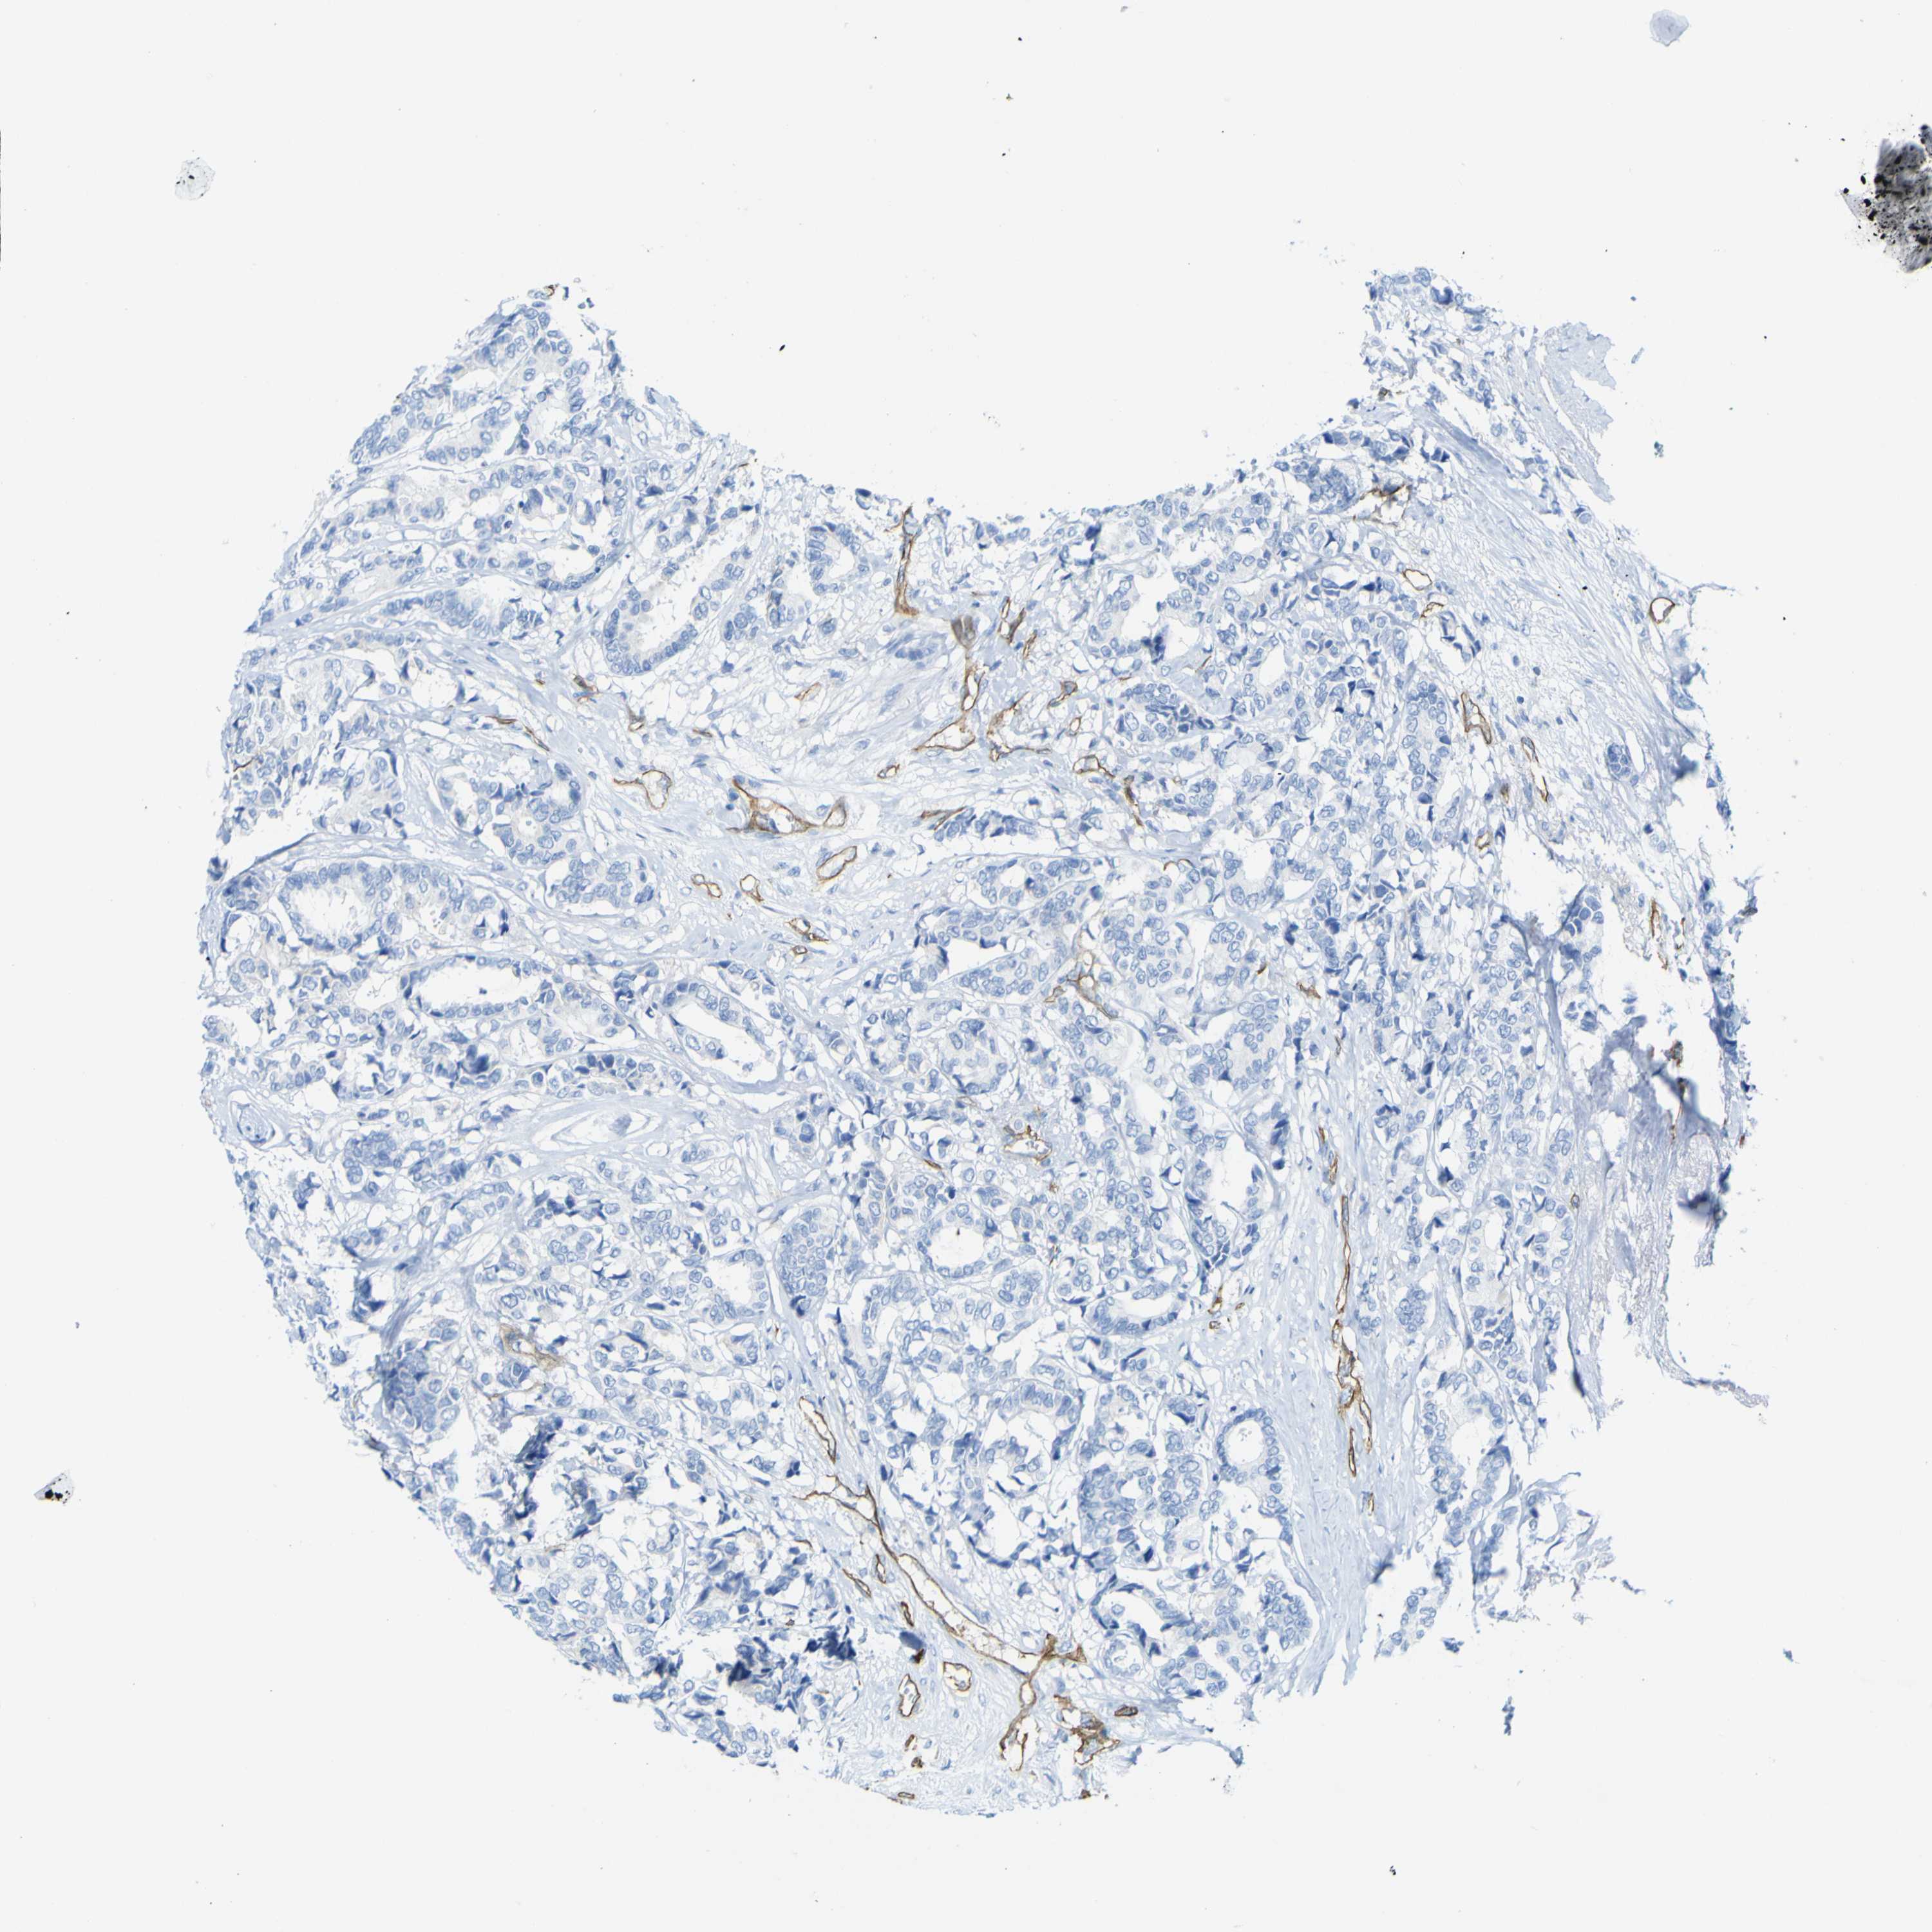

CANCER BREAST CANCER Show tissue menu

BRCA TCGA BRCA VALIDATION PROTEIN EXPRESSION

ANTIBODIES

AND

VALIDATION